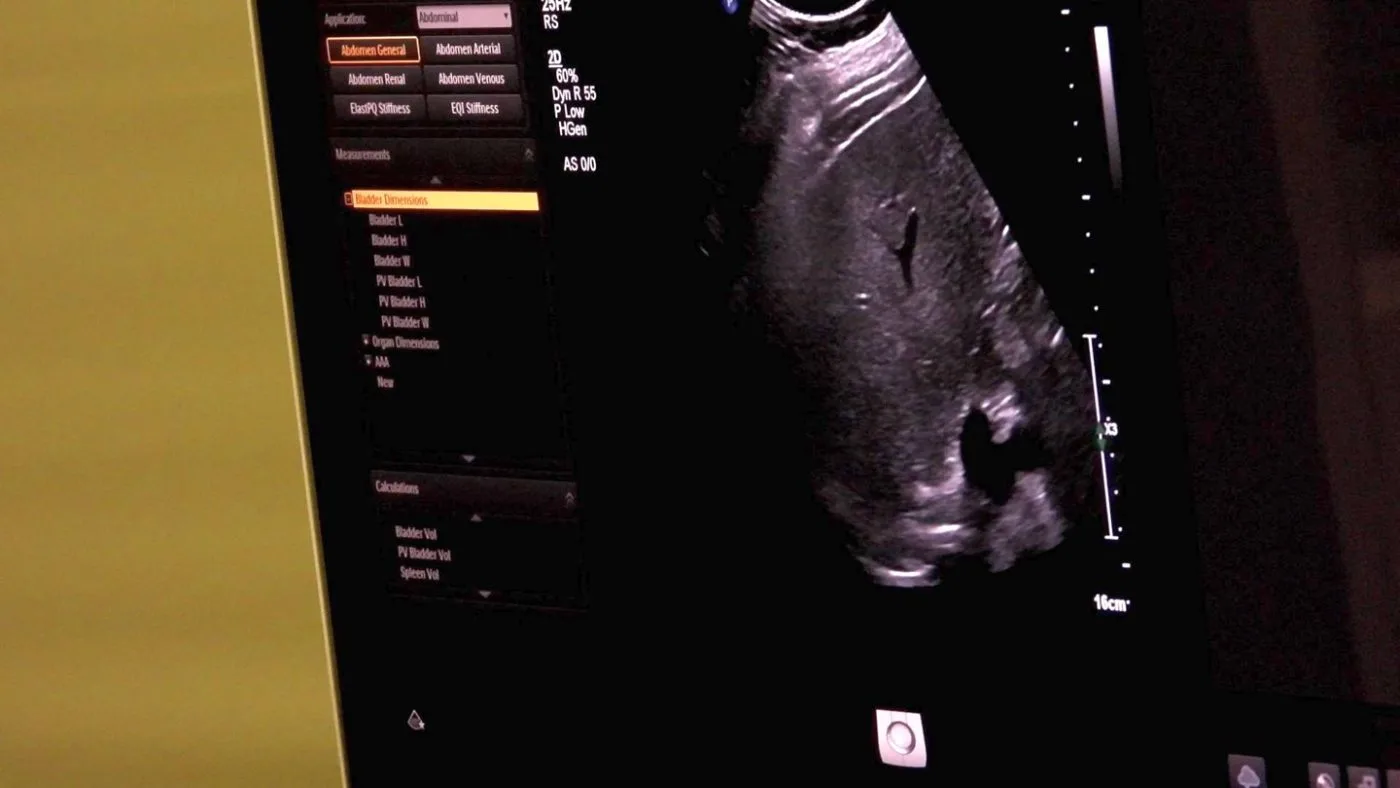

Sigurna i brza metoda dijagnostike

Ultrazvuk abdomena je jednostavna, bezbolna i sigurna metoda koja omogućava rano otkrivanje zdravstvenih problema poput cisti, tumora, masne jetre i kamenaca u žuči ili bubrezima. Rano otkrivanje značajno povećava šanse za uspješno liječenje i oporavak.